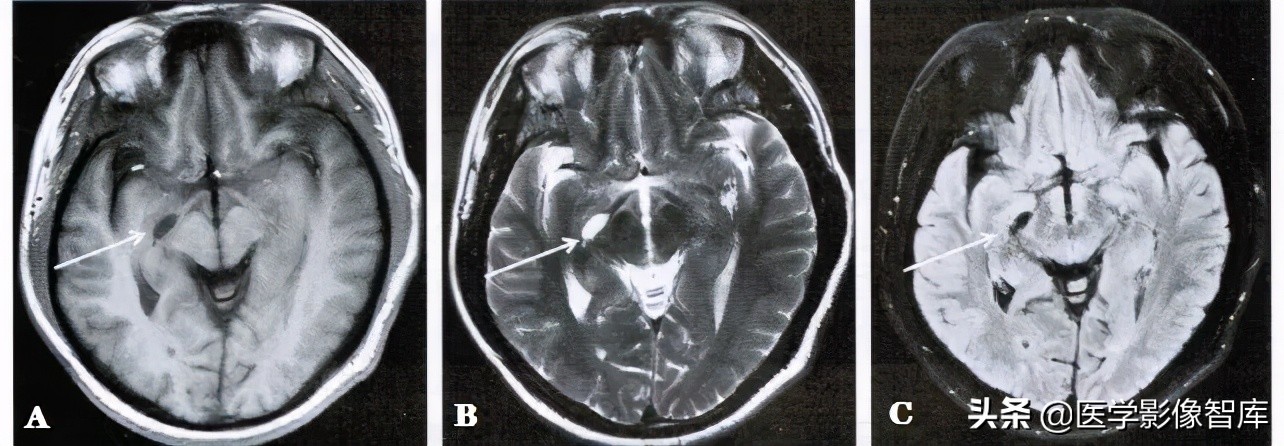

图1 右侧脉络膜裂囊肿

男性,51岁。 A. 轴面T1WI。 B. 轴面T2WI。右侧脑室颞角内侧可见一个冀状长T1、长T2信号影(箭); C. 轴面T2 FLAIR,囊肿在脑脊液抑制像呈低信号(箭)。